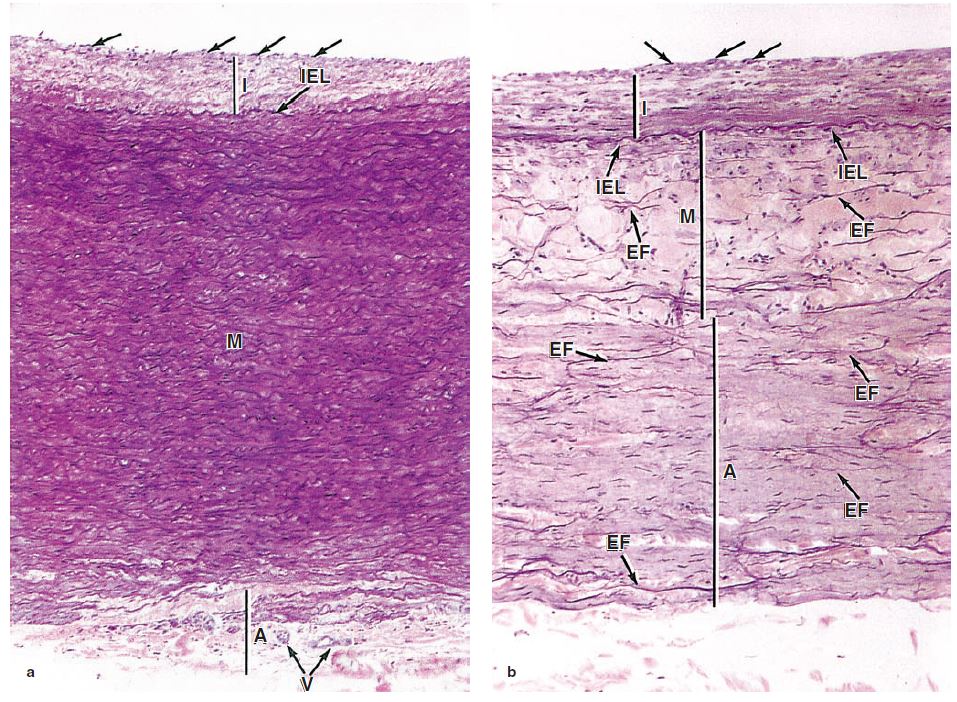

第一节 心血管系统 inner elastic membrane 中动脉(medium artery or

中动脉:中膜内平滑 肌纤维多达25~40层(肌 性动脉).

血管管壁的微细结构,除毛细血管外,其管壁结构一般分为内膜,中膜和

外膜:疏松结缔组织;有营养血管,分支进入中膜很厚,40 ~ 70层弹性膜